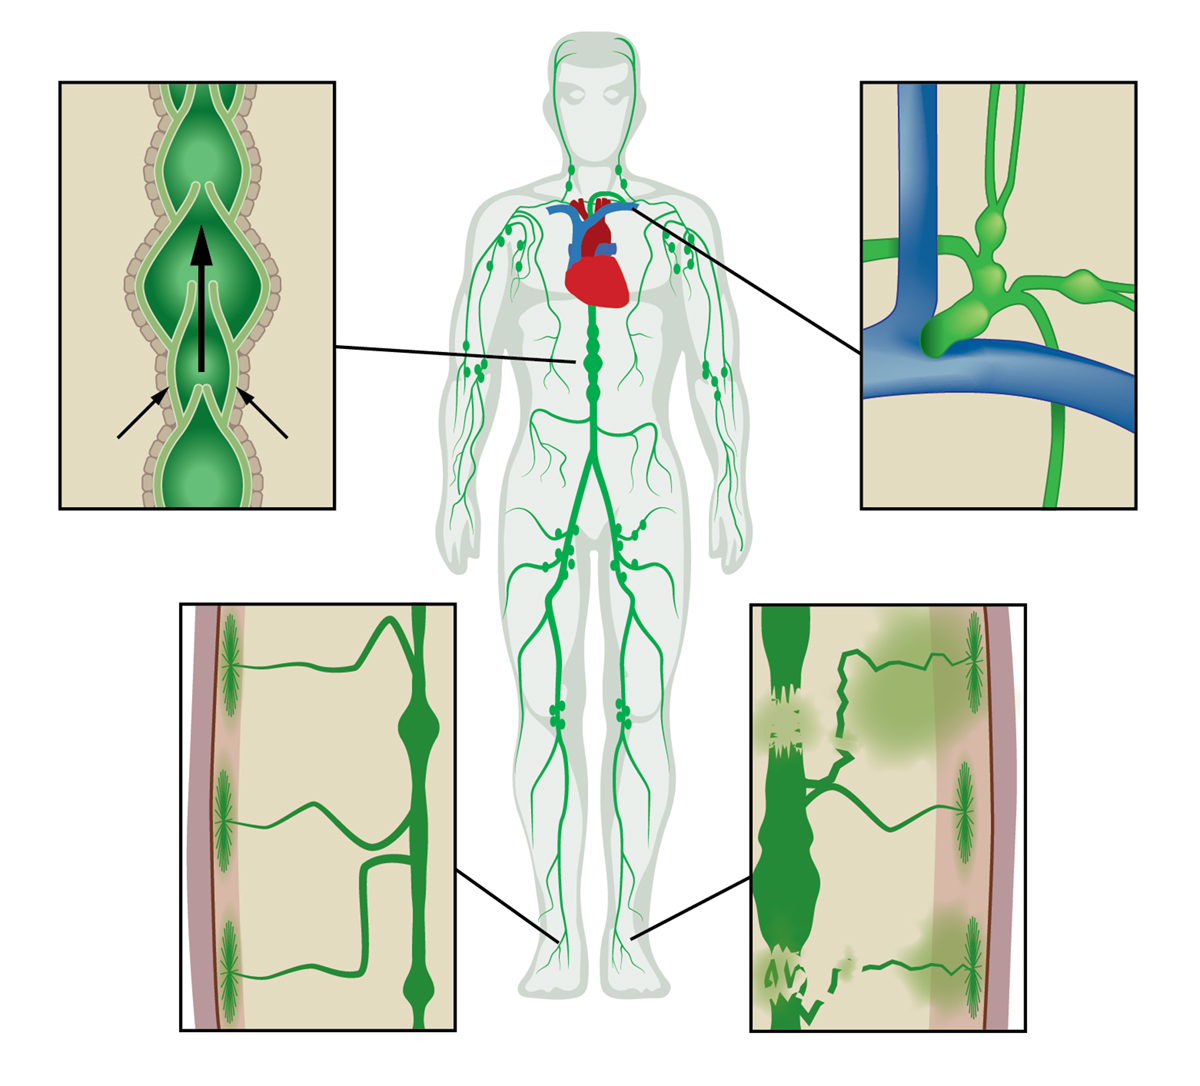

The lymphatic vascular system has largely escaped routine medical imaging and as a result, comparatively little is known about its role in health and disease. The open and unidirectional lymphatic system begins with the initial lymphatics that lie beneath the epidermis and line all organs. Waste products, immune cells and excess fluid (capillary filtrate) that enter the initial lymphatics are actively pumped through series of “lymph hearts” or contractile lymphangions that transit lymph through lymph nodes to the subclavian vein where the fluid returns to the blood vasculature (Figure 1).